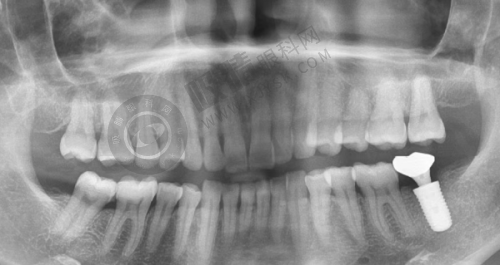

陕西省人民医院口腔科可开展全口数字化种植、ONLY 植骨术、骨劈开术、GBR 手术、即刻种植、上颌窦外提升等高难度的种植技术。